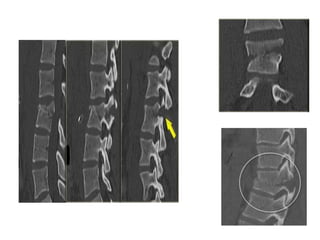

FLEXION-DISTRACTION = SEAT-BELT-TYPE = CHANCE #

• Posterior &middle columns failure.

(hyperflexion then tension forces)

• Anterior column 

- partial damage.

- functions like a hinge.

FLEXION-DISTRACTION = SEAT-BELT-TYPE= CHANCE # • Posterior &middle columns failure. (hyperflexion then tension forces) • Anterior column  - partial damage. - functions like a hinge.